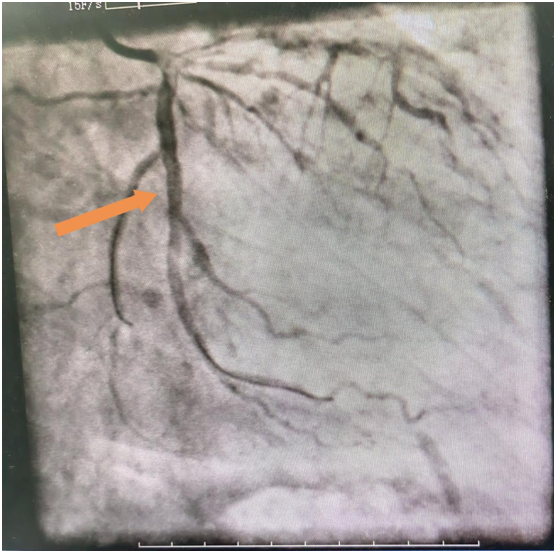

60岁的吴老伯患高血压病4年多,平时口服降压药物,没有规律监测血压,3年前患脑梗,治疗后好转,没有遗留明显后遗症,出院后没有规律服用药物治疗,出院时医师反复交代戒烟,吴老伯也没有放在心上。最近吴老伯在于熬夜后感头痛不适,起初头痛能自行缓解,随后感头痛症状反复发作,在快步行走及爬楼梯时明显,休息10多分钟可缓解,因症状反复发作,来到开阳县人民医院就诊,心血管内科医师在详细询问病史后,考虑吴老伯是冠心病高危人群,且头痛与活动相关,高度怀疑心绞痛,建议住院治疗,最开始吴老伯还很纳闷,明明是头痛来看病,怎么就变成心绞痛了?我没有胸痛啊!虽然心里有疑问,吴老伯还是接受医师的建议住院完善冠脉造影检查,果然冠脉造影明确了心脏回旋支有弥漫性狭窄,狭窄最重85%,前降支狭窄最重处75%,明确了头痛原因就是心绞痛。随即,心内科介入团队为吴老伯进行了回旋支支架植入术。植入支架后,吴老伯活动时头痛的症状也消失了。可以回家过个安稳的春节了。

冠脉造影结果

支架置入术后效果